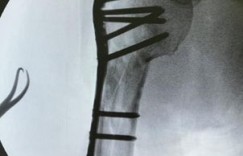

林志穎於今日晚間PO出兩張使用健身器材的照片,並表示「全力復健」,從照片上可以看到他戴著口罩、帽子,穿著一身黑的運動套裝,正在透過健身拉環來訓練手臂,而後在留言處PO出一張X光照,可以看出林志穎的手臂裡插滿了許多骨釘,這一幕也讓許多粉絲心疼不已,紛紛留言安慰,「加油,慢慢來不要急才好得快」、「加油,祝你早日康復」、「終於看到你分享照片了,加油,祝早日康復」、「加油加油,復健需要時間!我們都會陪小志一起,慢慢來,身體健康最重要!天冷也要多保暖唷」、「加油,慢慢來一定會恢復的,只是要時間」。

▲林志穎認真復健。(圖/翻攝自臉書/林志穎 Jimmy Lin)在林志穎PO出的健身房照片中,他穿著一身黑衣黑褲、黑口罩、黑帽子,正在認真地進行手臂鍛鍊運動。他寫下文字「全力復健」,引起部分網友好奇問「還沒好啊」,因而又在留言區PO出手臂X光片,秀出手臂放了鈦合金的樣子,多支鋼釘、鋼板的輪廓清晰可見。